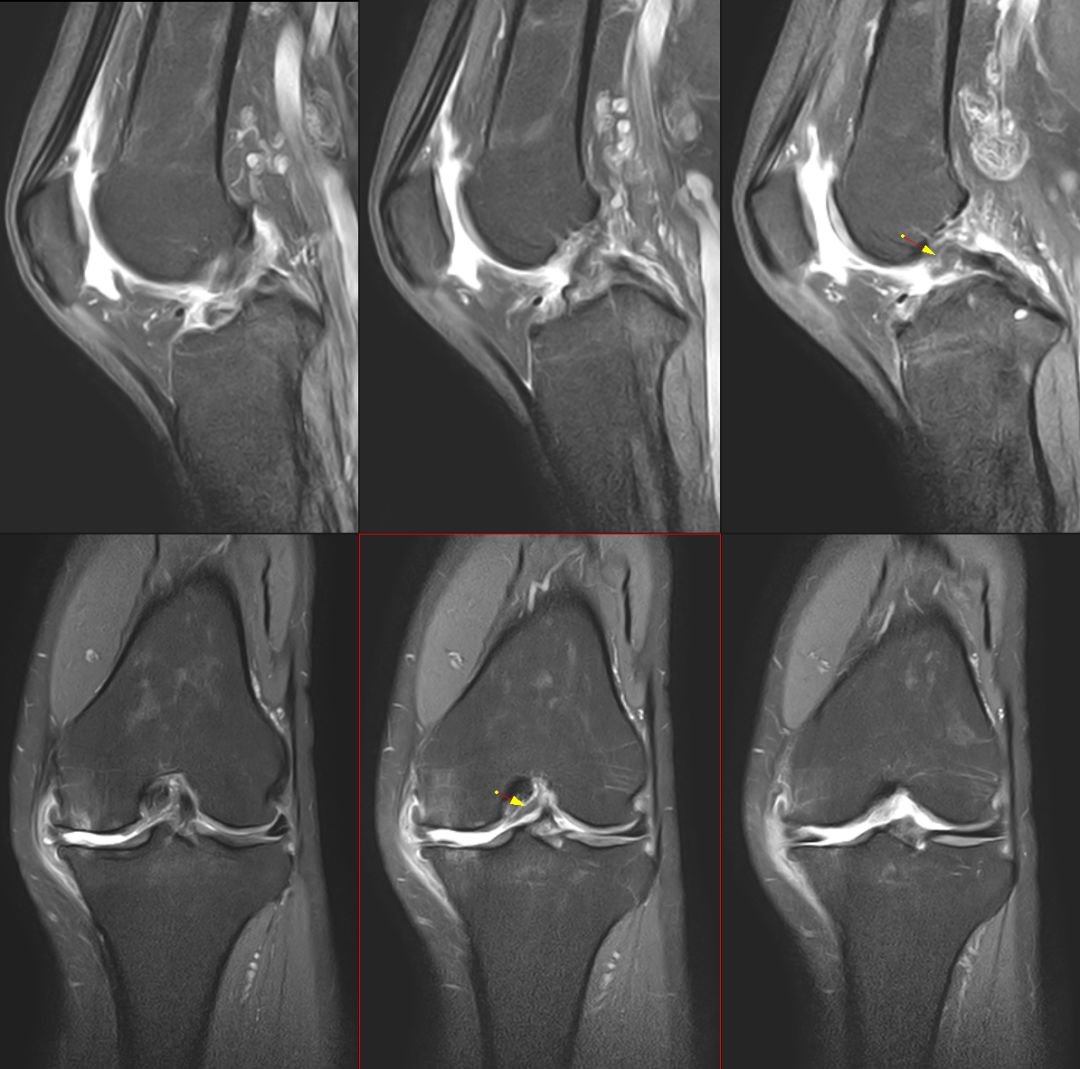

下图横断面的标线标记的是左下图,为外侧半月板的桶柄样撕裂移位

下图标记的是外侧半月板的撕裂

下图示外侧副韧带损伤 腘肌腱损伤 髂胫束连续

内侧副韧带损伤

膝后肌群损伤